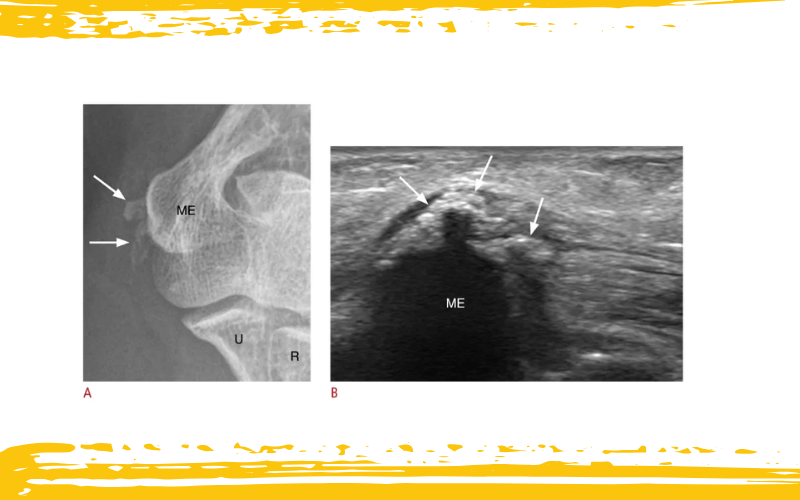

Radiografía e imágenes ecográficas (US) de una mujer de 61 años con tendinitis calcificante del tendón flexor común.

A. La radiografía oblicua del codo revela calcificaciones (flechas) en la inserción del tendón flexor común, cerca del epicóndilo medial (ME) del húmero.

B. La imagen ecográfica en eje largo del codo medial muestra un depósito calcificado dentro del tendón flexor común, que presenta sombra acústica posterior mínima.

U: cúbito (ulna); R: radio.